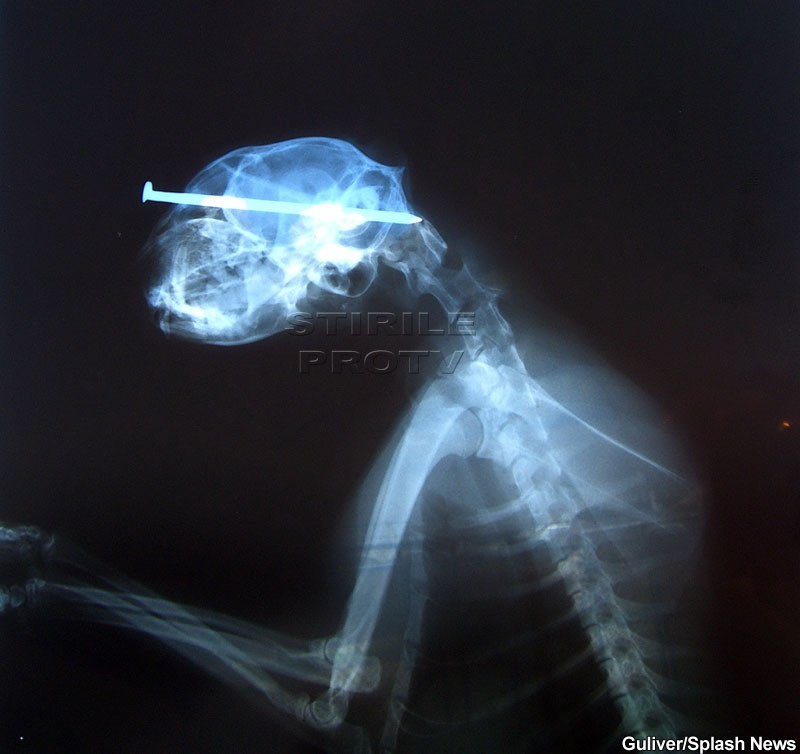

Amazing Grace a fost gasita in Iowa, America. Avea un cui infipt in crestet si nimeni nu intelege cum a supravietuit.

"N-am mai vazut niciodata asa ceva, iar faptul ca e in viata e pur si simplu miraculos", spun cei de la Protectia Animalelor, care au avut grija de pisica.

Amazing Grace a ajuns pe mana unui chirurg, care a operat-o si i-a scos cuiul.